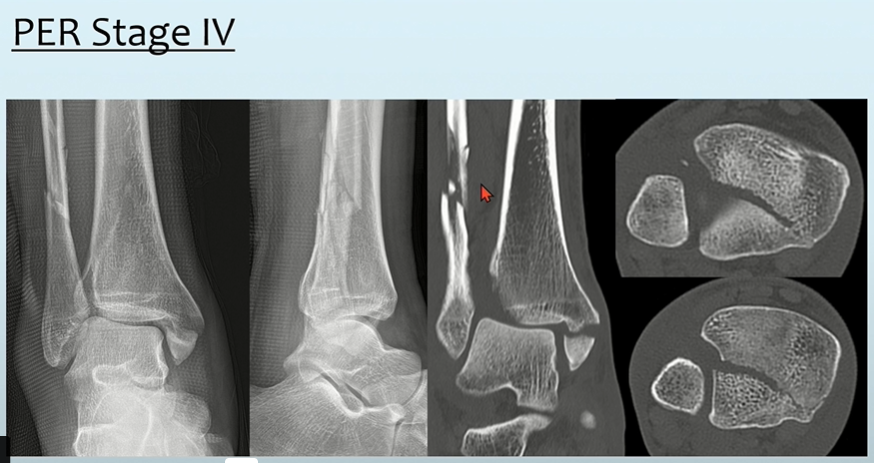

- Stage3: high fibular fracture (굉장히 특징적입니다. 높이는 Danis-Weber classification상 C)

- Stage4: PM 또는 PTIFL injury

실제 영상보면, high fibular fracture가 특징적입니다.